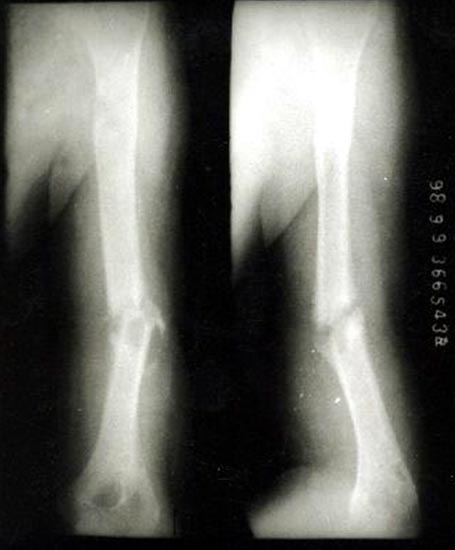

病例二、患者女性,20岁,肱骨中段骨折1年,骨不连形成。

带锁髓内钉固定骨折端提供支撑力,患者自体骨髓细胞经与松质骨和骨生长因子复合,

使没有细胞的植骨材料变成了有细胞的活骨。骨折在8个月后愈合。

手术后去除内固定